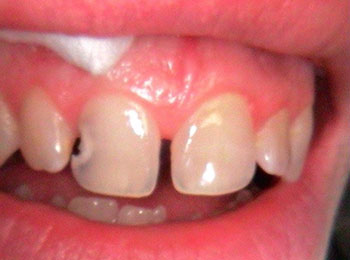

Bonding is an option for chipped or cracked teeth as well as an occasional alternative to veneers in certain cases. It is a process in which a series of composite materials of varying shades, tints, opacities and physical properties are used to precisely replicate any missing tooth structure. These next-generation materials are bonded to the tooth's surface, sculpted into shape, hardened, and then polished to match adjacent teeth.

Before bonding

After bonding